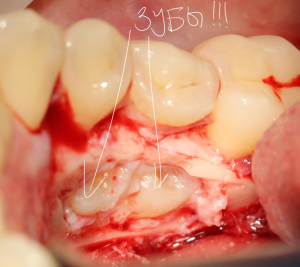

А вот они! Далее мы руководствуемся главным правилом хирурга-стоматолога:

Вот удаленные зубы:

А вот их лунки: